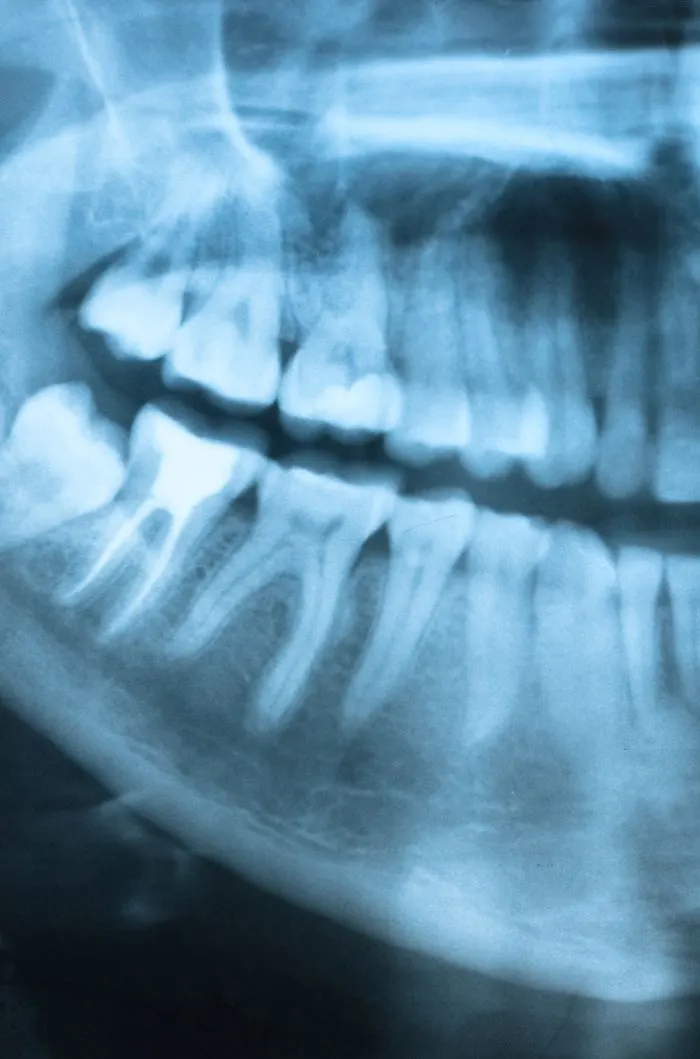

With digital x-rays, we get high-resolution images of your teeth that allow us to make more accurate diagnoses. When you’re in pain or experiencing an emergency, we can see why the tooth is reacting and if an extraction is needed.

During your consultation, we’ll take digital x-rays to assess the condition of your tooth and the surrounding bone. We’ll explain whether extraction is truly necessary and walk you through any alternatives. If you’re moving forward, we’ll review the number of teeth to be removed, aftercare expectations, and any follow-up recommendations for tooth replacement. We’ll answer every question you have so you feel fully informed and know what to expect.